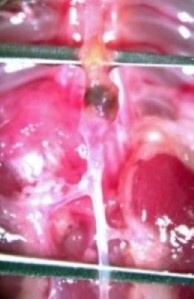

A formations, 28 Days Ang II, 90 Days 60% High Fat Diet

Abdominal Echo's performed 24 hours prior to sac using VisualSonics Vivo 2100